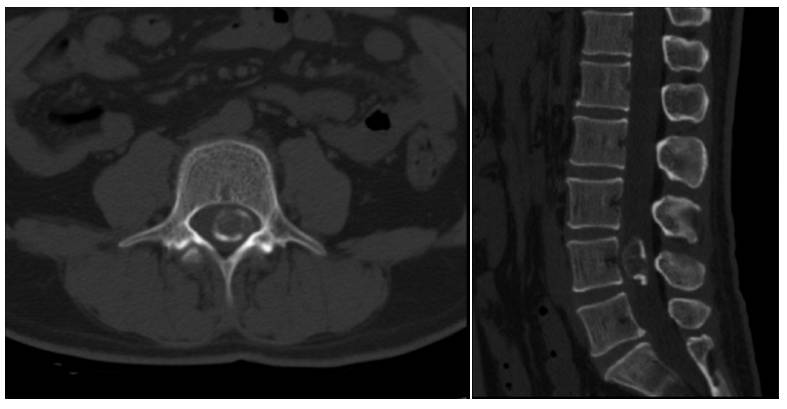

患者术后恢复可,术后左下肢疼痛消失,行走无殊。但出现轻度麻木,考虑神经与钙化壳粘连严重有关。复查腰椎CT及腰椎增强MRI显示肿瘤基本全切除(图2)。

图2. 术后CT及MR